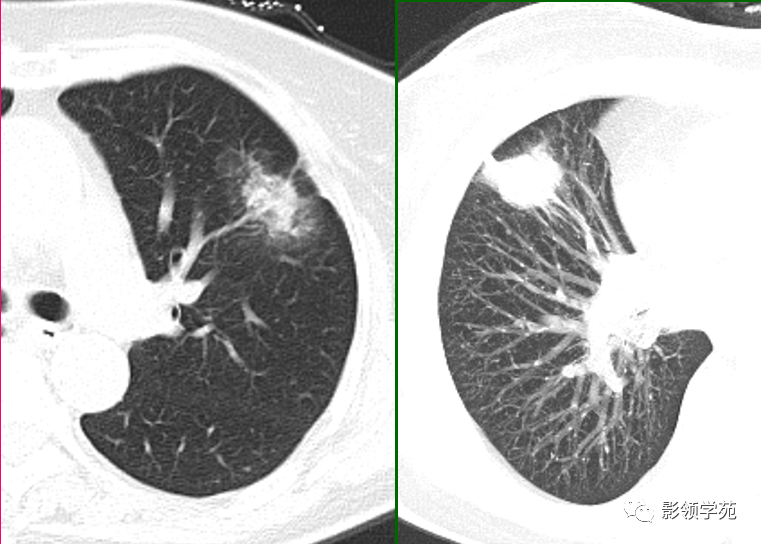

肺结核的渗出性改变:片状、边界模糊

有硬化部分的磨玻璃样变